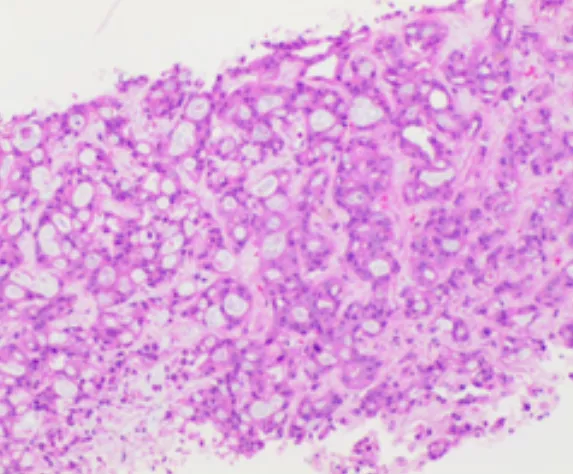

肝內(nèi)病灶穿刺組織病理結(jié)果

(肝內(nèi)病灶穿刺組織)肝組織內(nèi)見腺癌浸潤,免疫組化結(jié)果:CK7(+),CK19(+),Ki-67(約30%+),P53(彌漫強+),CEA(部分+),TTF-1(-),結(jié)合病史及影像學檢查,首先考慮胰腺癌轉(zhuǎn)移。